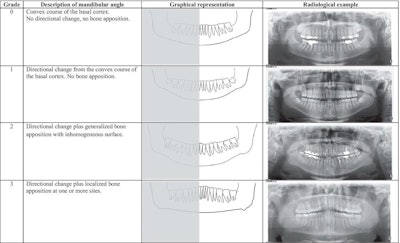

Grade, description, graphical representation, and radiological example of bone apposition at the mandibular angle. Image courtesy of Turp et al. Licensed under CC BY 4.0.

Bony changes were found in 95 mandibular angles of 59 adults with bruxism. Though the degrees of apposition varied, almost two-thirds of these patients had bilateral bony changes. Except for two mandibular angles viewed, each bone apposition was partnered with a directional change of the corresponding lower jaw angle. As expected, no bony changes were seen on the children's x-rays, the authors wrote.

When dental x-rays show bony changes at patients' mandibular angles, the changes should be interpreted as a functional adaptation to the long-term increased loads that occur when the jaw-closing muscles contract due bruxism, the authors wrote.